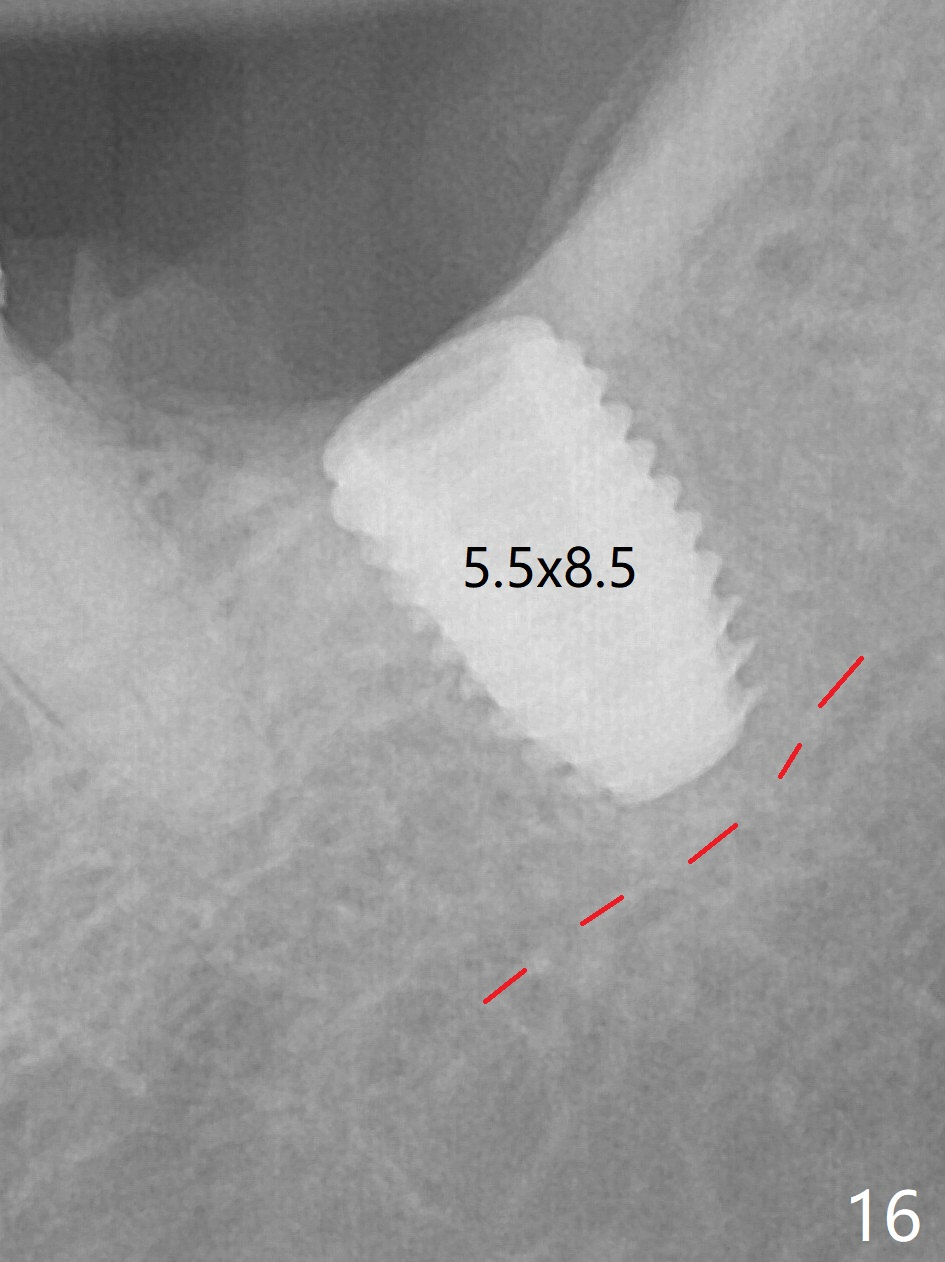

There is no apparent bone loss 4 months postop (Fig.10).  There is chewing pain in spite of occlusal adjustment 7 months post cementation (Fig.11-13: increased radiolucency around the implant).  The crown/abutment is removed and a healing abutment is placed (6x3 mm); the implant is stable.  The patient return for re-evaluation in 3 months (15 months postop); radiolucency appears to reduce (Fig.14).  But there is pain when the healing abutment is being removed.  After local anesthesia, the implant is removed with a wrench.  Following debridement of the osteototomy (intact, although tender), a 5x10 mm dummy implant with SLA surface is placed (Fig.15).  After 5.5 mm tap, a 5.5x8.5 mm implant is placed with >50 Ncm (Fig.16).  A 6.8x5 mm healing abutment is placed, followed by periodontal dressing.  Re-analysis of preop CBCT shows that the bone density at the site is low: 70 units average.  Progressive loading is necessary for this case 4-6 months postop.  The soft and hard tissues around the implant seem to heal 4 months postop (Fig.17).